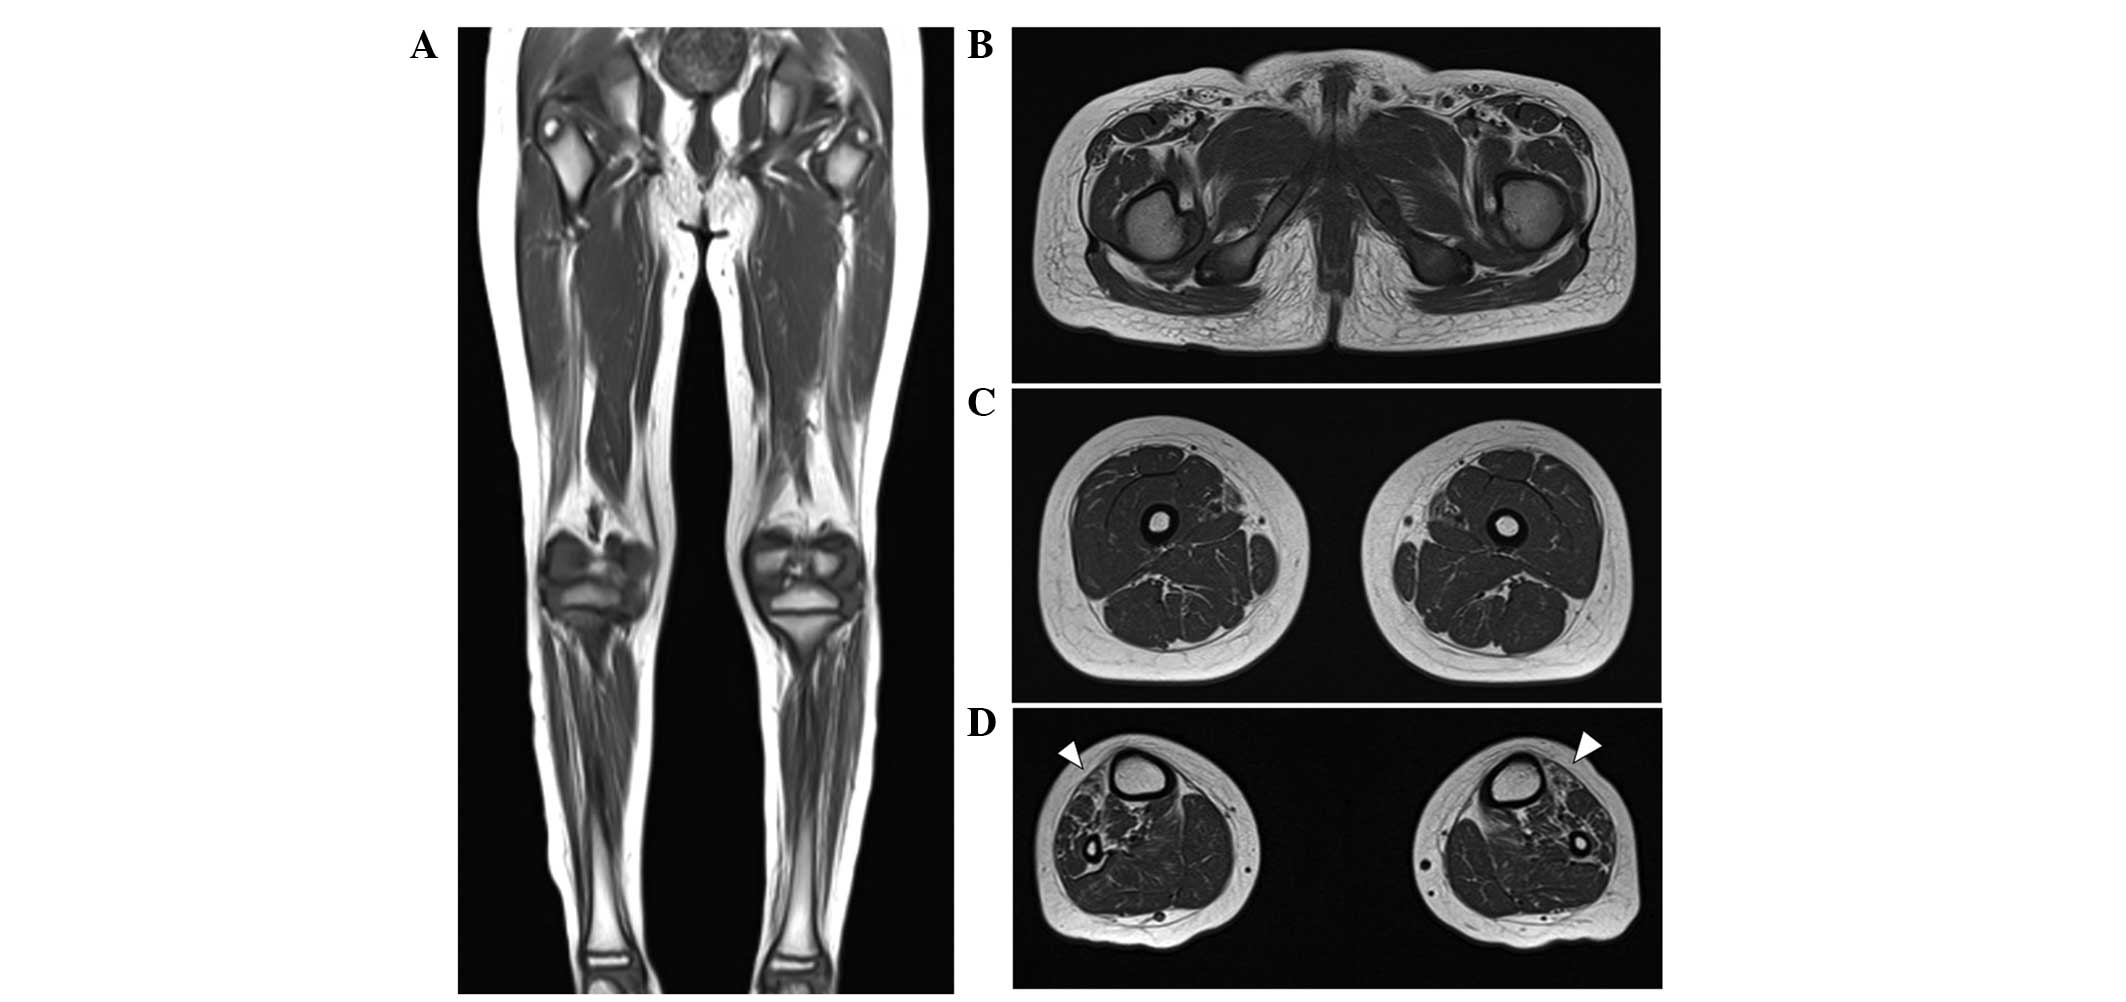

Length-dependent patterns in the lower extremity MRI

At the age of 10 years, T1-weighted MRIs indicated muscle atrophy and fatty replacement in the lower calf muscles but close to normal hip and thigh muscles. These findings are compatible with length-dependent axonal degeneration. In addition, fatty replacement of the calf muscles was predominant in the anterior compartment, including the tibialis anterior muscle, consistent with his foot drop and steppage gait (Fig. 3A–D). A brain MRI performed when he was 8 years old indicated the cerebral cortex and cerebellum were normal in structure and size.

Figure 3

Lower limb MRI of the proband. T1-weighted (A) coronal and (B–D) axial images of a lower limb MRI. (B and C) There was minimal fatty infiltration of the other compartments of the lower legs and no prominent abnormal findings in the hip or thigh muscles. (D) However, fatty infiltration and muscle atrophy (arrowheads) were prominently evident in the anterior compartment of both lower legs. MRI, magnetic resonance imaging.